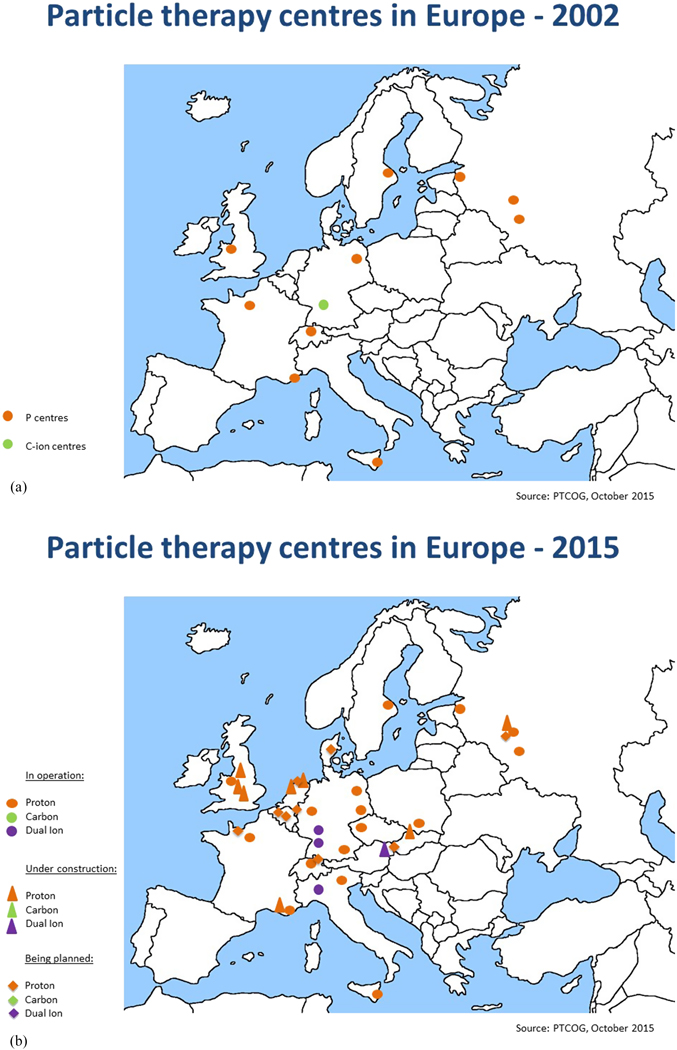

It is clear that the focus of R&D for hadron therapy has shifted since ENLIGHT was first established, if only for the simple reason that the number of clinical centres has increased dramatically—particularly for protons (figure 9). In Europe alone there are currently around 20 centres at various stages from approved to operational, and the number is set to double by 2020. The same trend is reflected globally, with around 50 centres currently planned or operational, and this is set to increase to 100 by 2020 (figure 10). To date, some 150 000 patients have been treated with protons and more than 20 000 have been treated with carbon ions.

Figure 9. This picture shows the distribution and number of hadron therapy centres in 2002 in Europe when the ENLIGHT network was launched and the distribution and number of centers in 2015, illustrating the increasing interest in particle therapy (http://www.ptcog.ch/index.php/).